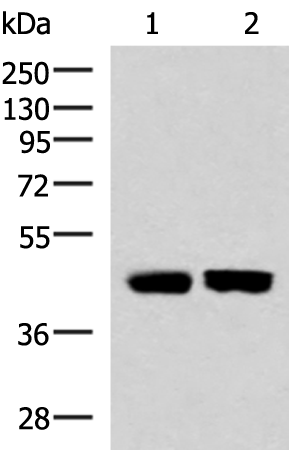

分类: 科研抗体货号: P03309别名: PSF3应用: WB,IHC反应种属: Human, Mouse